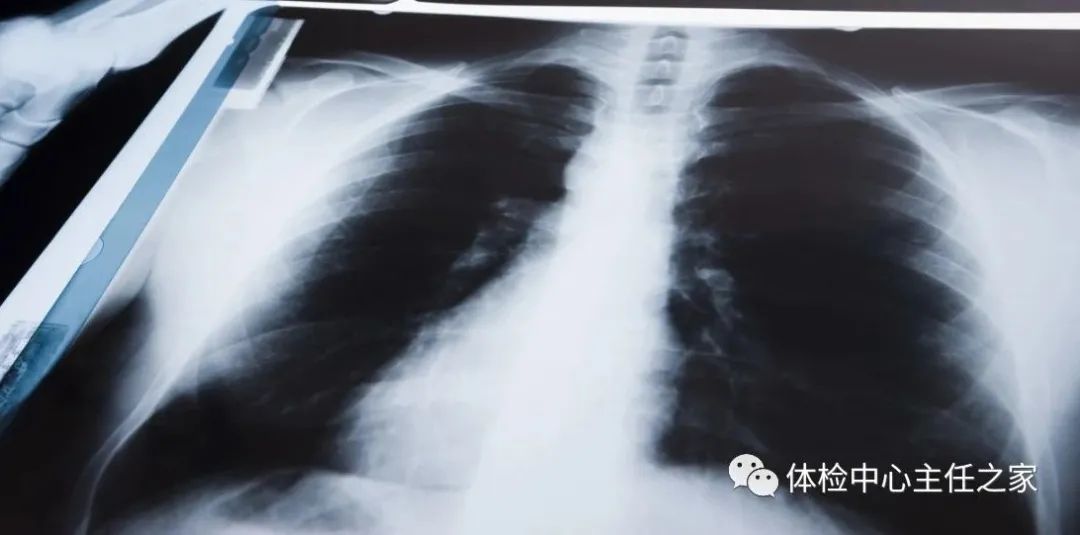

胸部X线可以检查心、肺、纵隔、肋骨、胸膜及主动脉等,比如肺纹理增多、肺部钙化点和主动脉结钙化等均可通过X线检查。

相比X线,胸部CT检查显示出的结构清晰度更明显,对胸部病变的检出敏感性和显示病变的准确性均优于常规X线胸片。胸部CT检查还有利于检出轻微病变和隐蔽部位病变,显示病变特征,尤其是对早期肺癌的确诊有决定性意义。然而,值得一提的是,CT检查的辐射剂量显著高于X线。

X线胸片可粗略检查心脏、主动脉、肺、胸膜和肋骨等,可以显示有无肺纹理增多、肺部钙化点及主动脉结钙化等。

胸部CT检查显示出的结构更清晰,对胸部病变检出敏感性和显示病变的准确性均优于常规X线胸片,特别是对于早期肺癌确诊有决定性意义。

但是CT检查的辐射剂量高于X线。而MRI对于肺部疾病的诊断,应用非常有限。